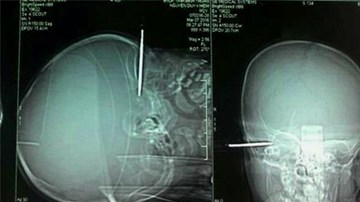

Cứu sống bé 14 tháng bị tuốc nơ vít đâm xuyên sọ

18h, ngày 7/3, Bệnh viện đa khoa Bình Thuận tiếp nhận cháu trai tên Nguyễn Duy Khiêm 14 tháng tuổi bị tuốc nơ vit đâm xuyên sọ sâu 1,5 cm. Ngay sau đó, các bác sĩ kịp thời phẫu thuật lấy tuốc nơ vít ra. Theo giới chuyên môn, nếu không kịp thời xử lí, cháu bé có thể bị nhiễm trùng não và tình trạng sức khỏe có thể xấu đi nhiều. Hiện bé tỉnh táo và đang được bệnh viện tiếp tục theo dõi, điều trị.